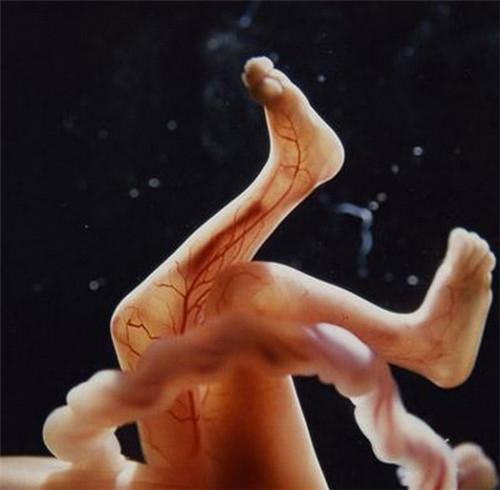

第16周

透过薄薄的皮肤,血管清晰可见.

第18周,胎儿可以感知来自外部的声音